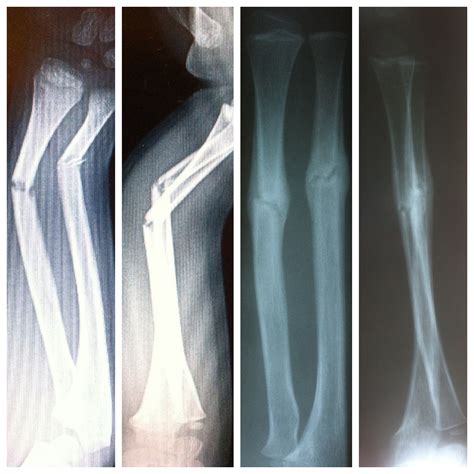

Fractured Ulna And Radius Bones

• Imaging Tests: X-rays are the primary diagnostic tool for identifying fractures. In some cases, additional imaging tests like CT scans or MRIs may be required for a more detailed view.

Imaging tests are crucial for determining the type and severity of the fracture, which will guide the treatment plan.

Types of Ulna Fractures

Ulna fractures can be classified into different types based on their location and pattern. Common types include:

• Proximal Ulna Fracture: Occurs near the elbow joint.

• Midshaft Ulna Fracture: Occurs in the middle of the ulna.

• Distal Ulna Fracture: Occurs near the wrist joint.

• Open Fracture: The bone breaks through the skin, increasing the risk of infection.

• Closed Fracture: The bone breaks but does not penetrate the skin.

• Comminuted Fracture: The bone shatters into multiple pieces.

• Greenstick Fracture: Common in children, where the bone bends and partially breaks.